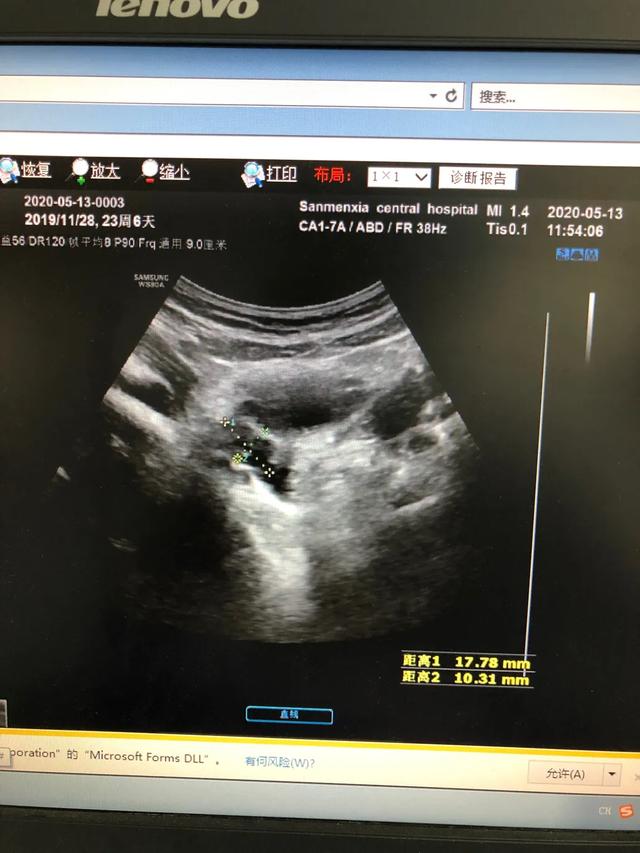

下图是一例患儿性早熟的B超结果、胸片结果及血清学化验结果。

从检查结果来看,B超显示子宫卵巢有囊性回声;胸片显示乳腺发育;而血清学指标,促黄体生成素的峰值是13.09,促卵泡的峰值是20.91,LH/FSH=62.60%。